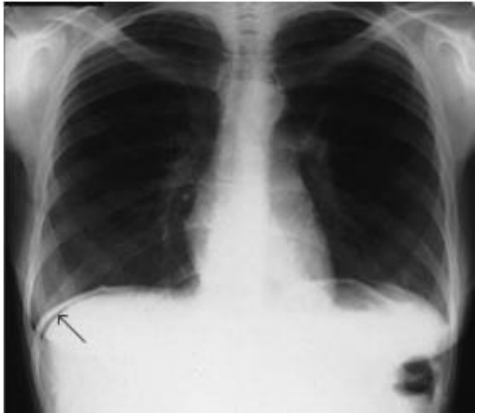

Radiografia do tórax em posição ortostática demonstrando pequeno pneumoperitônio (seta).